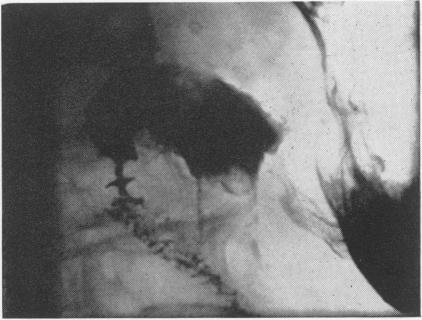

Congenital duodenal stenosis in a patient aged 78 years.

Gut. 1967 Jun;8(3):313-4. doi: 10.1136/gut.8.3.313.